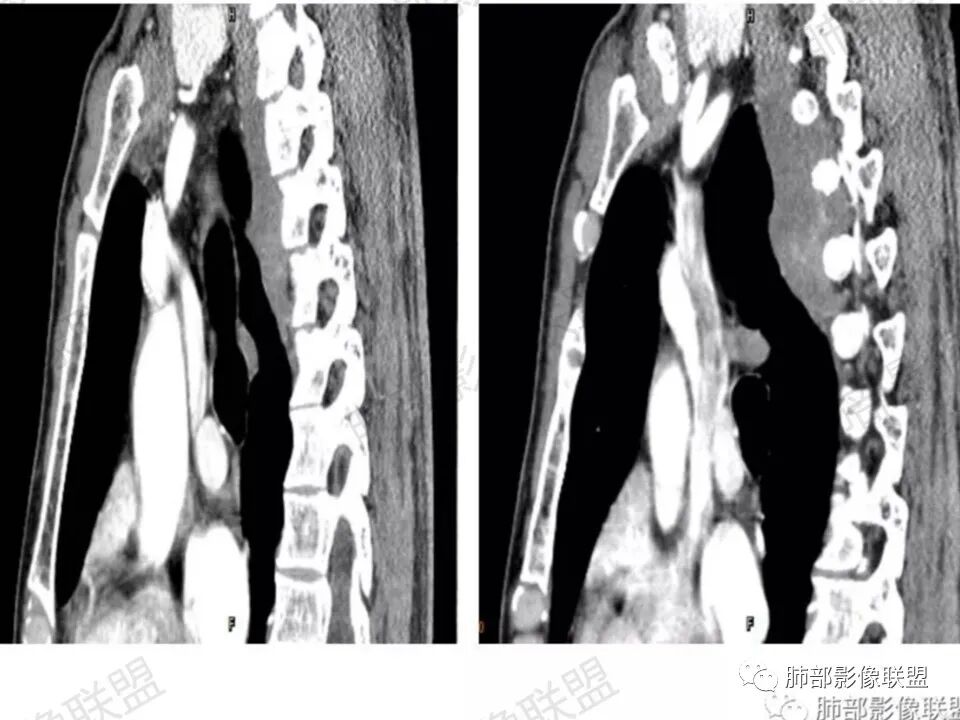

后纵隔脊柱旁占位,病灶内有低密度区,增强扫描不均匀强化,失状位似沿神经走形,部分进入锥间孔,首先考虑神经源性肿瘤。

患者,男性 45岁,反复背部疼痛3年。右侧后纵膈脊柱旁软组织影,匍匐样生长,临近骨质未见破坏征象,软组织局限性隆起,椎间孔未见明确扩大。增强呈渐进性升高,内部强化不均匀,未见坏死、囊变。结合病史,总体考虑良性病变,神经来源,神经鞘瘤可能。

问:这个病例病灶确实邻近椎间孔生长,除了神经源性肿瘤会向椎间孔方向生长,还有什么肿瘤会有这种行为?这个病灶整体形态呈扁平不规则,周围骨质未见破坏,就一定是良性吗?    答:这个病灶明显嵌入式生长,往往提示病灶柔软或有侵袭性,而神经鞘瘤往往有包膜,有张力,典型的形态往往呈类圆形、“逗点形”或“哑铃型”横向延入某一椎间孔内;神经节细胞瘤虽然可以比较柔软,但是具有大量粘液基质,动静脉期强化不明显,延迟强化轻度增强,加之没有钙化,故符合点不多;此外比较柔软的肿瘤如淋巴瘤,但是周围没有肿大淋巴结不太考虑;本例形态不规则的实性肿块,没有明显骨质破坏,倾向具有侵袭性的间叶来源的肿瘤。

答:神经源性肿瘤的解剖位置及形态很重要—沿神经干方向生长走行。后纵膈内神经鞘瘤最常见的是神经根出入椎间孔处,并可沿着肋间神经方向分布,所以后纵膈神经鞘瘤通常横径大,上下径小,这个病例明显上下径长,所以不符合神经鞘瘤;神经节细胞瘤可沿着椎旁上下方向分布(参见上图黄色梭形的神经节),所以表现为上下径长,虽然生长方式符合,但是节细胞瘤以粘液为主,易钙化,该病例成分及强化方式不符合。